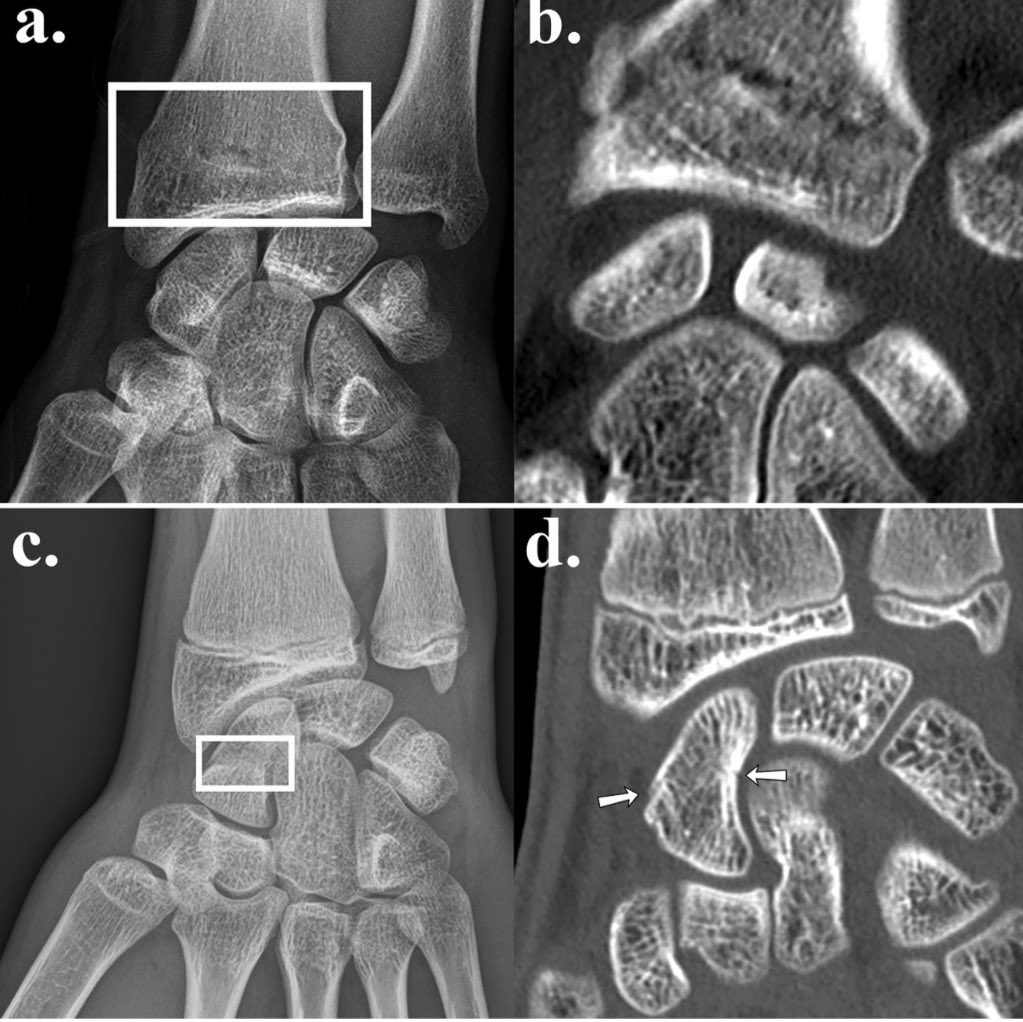

Vu qu’on utilise l’IA en radiologie en routine depuis des années, je commence à voir un effet qui était prévisible mais qu’on a encore du mal à quantifier: le deskilling (ou perte en compétence) et ça touche en premier lieu les non radiologues. C’est quoi? Je vous explique. Je parlerai ici surtout de l’IA d’aide à la détection des fractures en radiographies, qui est un des premiers domaines où on a eu des algorithmes commercialisés et qui répond à une vraie demande notamment dans les filières d’urgence, pour aider au tri et à un diagnostic rapide. Image